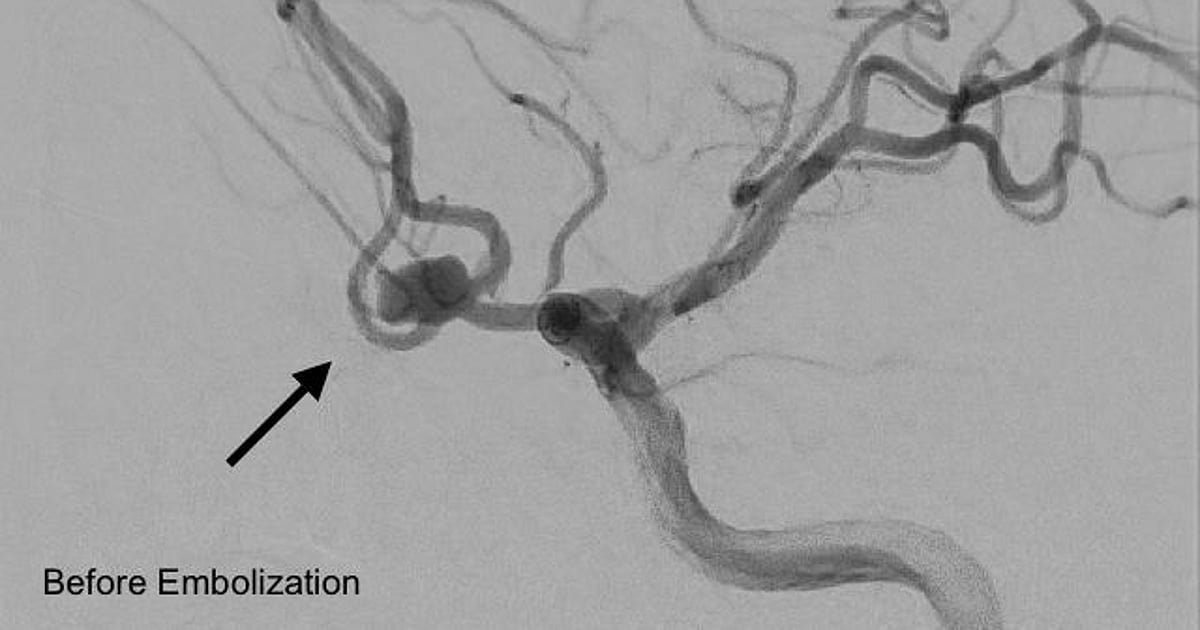

مستشفى المانع بالأحساء ينجح في تنفيذ أول إجراء لإغلاق تمدد شرياني دماغي بالقسطرة

حقق مستشفى المانع بالأحساء إنجازًا طبيًا بنجاح تنفيذ أول إجراء من نوعه لإغلاق تمدد شرياني دماغي نازف بالقسطرة لمريض يبلغ من العمر 45 عامًا، جرى تحويله من مستشفى آخر إثر إصابته بنزيف حاد في الدماغ.